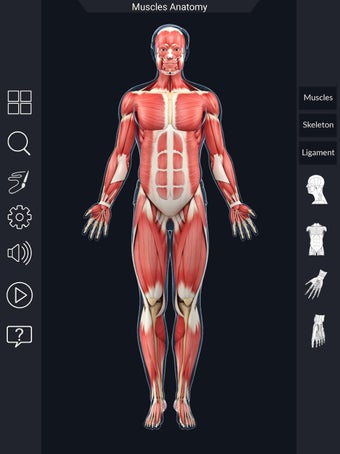

Den mest omfattande mobilappen som finns i världen för att studera muskelanatomi, som låter dig rotera 360°, zooma och flytta kameran runt en mycket realistisk 3D-modell.

Det finns mycket detaljer tillgängliga för varje muskel, vilket gör det till ett utmärkt verktyg för medicinstudenter.

Det finns många verktyg tillgängliga för varje muskel, inklusive: